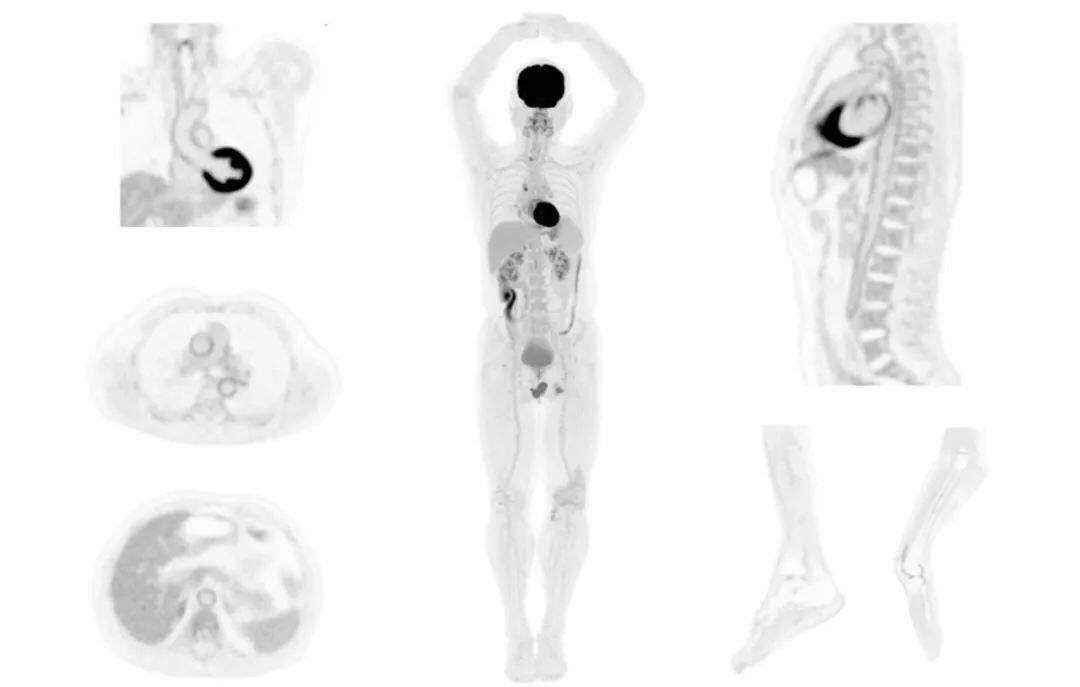

uExplorer探索者不再局限于傳統(tǒng)靜態(tài)代謝過程3D成像,而是在此基礎上新增一個維度——時間,從而實現(xiàn)4D全景成像。

注射總劑量為7.8mCi,14分鐘全身采集時間,在擁有超高靈敏度與超高分辨率的uEXPLORER上,即可得到展示顯示人體諸多精細結(jié)構的高清三維圖像。

注射總劑量為7.8mCi,注射后1.6小時,基于uEXPLORER探索者掃描1分鐘的圖像

注射總劑量為0.67 mCi FDG(低于常規(guī)劑量的十分之一),基于uEXPLORER探索者掃描15分鐘的圖像

注射總劑量為6.9mCi,注射后10小時,基于uEXPLORER探索者掃描14分鐘的圖像